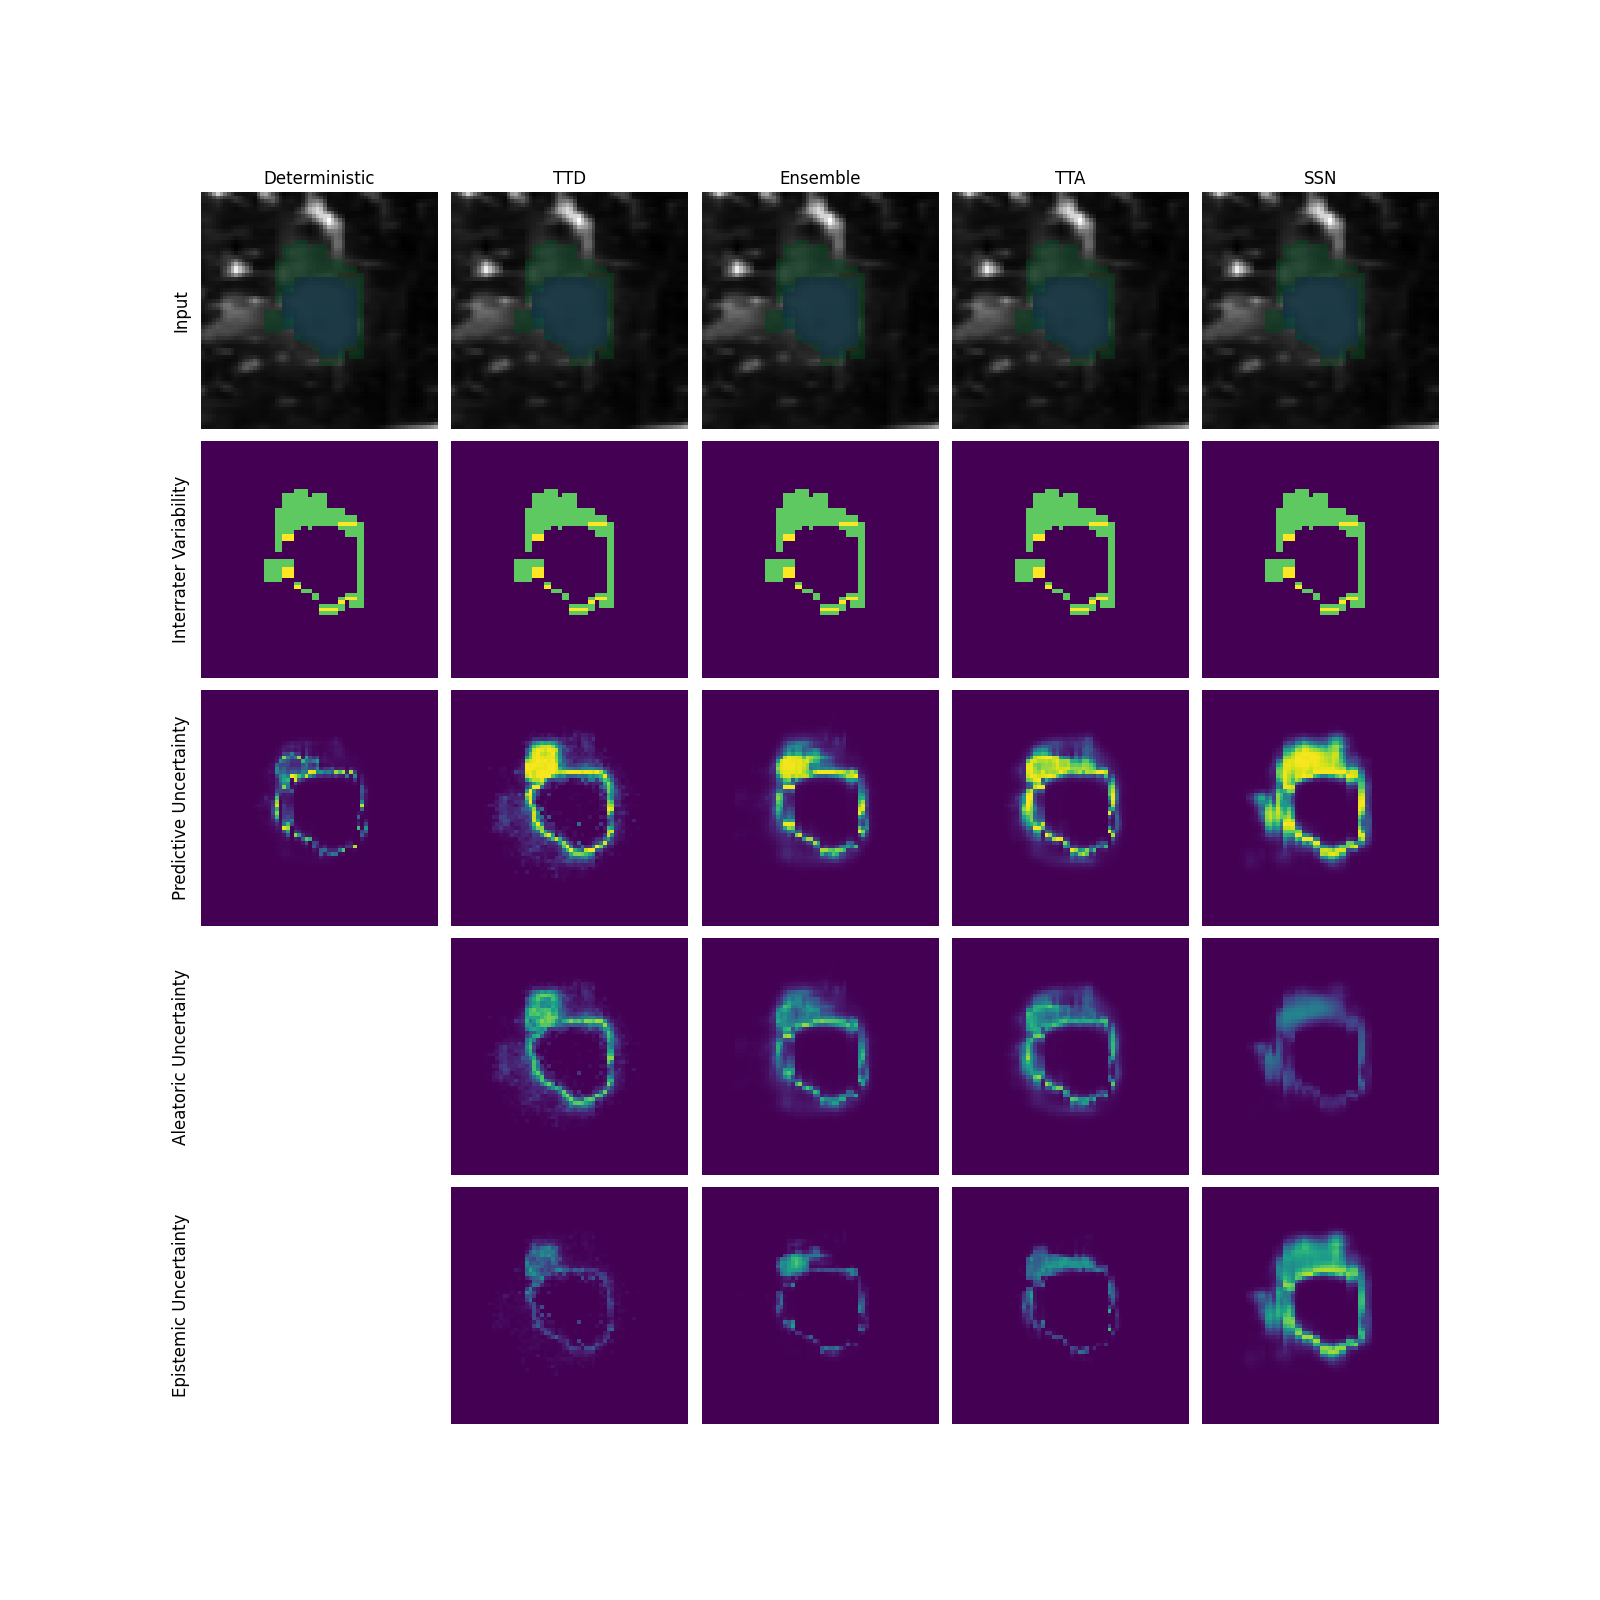

Q1 + Q2: For assessing the capability of uncertainty methods in capturing AU, we employ the normalized cross-correlation (NCC) as a quantitative measure between the predicted uncertainty map and the reference uncertainty map based on the disagreement of multiple raters (for details see Appendix A). Additionally, we perform qualitative inspections of the uncertainty maps. Based on the theory, successful separation of uncertainties would imply AU-measures to exhibit high NCC and high qualitative fidelity (Q1 = ”yes”) and vice versa for EU-measures (Q2 = ”no”).

The general findings of the uncertainty separation study are summarized in Figure 2a, while underlying results are shown in Figure 2b for the toy dataset and Figure 3 (see gray-shaded ”Q” indicators on respective panels) for LIDC and GTA5/CS. More detailed descriptions and results as well as a qualitative analysis of uncertainty maps are provided in Appendix G.

Modeling aleatoric uncertainty (Q1 + Q2) While AU-measures clearly captured AU much better than EU-measures for the toy dataset, this behavior is inconsistent on the real-world datasets. On the LIDC datasets with AU stemming from rater ambiguity, which mostly occurs at the border of structures, the benefit of separating AU-measures from EU-measures is not evident when examining the NCC scores. For GTA5/CS, where induced label ambiguities span entire spatial structures, the AU-measures generally capture AU better than EU-measures. However, the absolute NCC scores from the AU-measures vary greatly across prediction models. We attribute this to SSNs capturing the widespread label ambiguities, while other models overemphasize the border regions.

Modeling epistemic uncertainty (Q3 + Q4) While EU-measures capture EU better than AU- and PU-measures on all datasets, the benefit of this separation varied greatly depending on the AU in the respective training and test data. More specifically, when more AU is present in the i.i.d. training and test data, the benefit of EU- over AU- and PU-measures increases as the ambiguity modeling in the i.i.d. setting is separated from the EU-measure. This connection can also be observed on GTA5/CS, where the captured AU induced by spatially widespread ambiguities translates to a higher EU-measure performance compared to LIDC.

General Insights. Although both, AU- and EU-measures, mostly do behave as expected, the extent of achieved separation depends on the data set properties such as the presence of ambiguities in i.i.d and/or OoD cases. As theoretically motivated in Appendix E, we observe that TTA is in fact most suited for modeling EU, resolving a controversial debate in current literature. We base this on the behavior of our derived EU-measure for TTA being very similar to ensembles and TTD, often even outperforming TTD. The comparable performance to ensembles renders TTA often a cheap alternative for estimating EU. For SSNs, our proposed EU- and AU-measures perform as intended on the toy dataset and GTA5/CS. Whereas on LIDC, the ambiguity, which is mostly present in the border regions, seems to be captured by EU-measures.

LIDC datasets. On the LIDC datasets, EU-measures performance is similar to that of AU-measures. Therefore the approaches seem to model EU in the areas attributed to AU (Q2).

In fact, for SSNs, the AU-measure even shows a lower NCC than the EU-measure, which could be attributed to the SSNs rating the border regions with high EU, which are the regions of disagreement.

The qualitative analysis indicates that a slightly better separation between AU and EU becomes apparent when there is meaningful inter-rater variability beyond small border regions (see Figure 10).